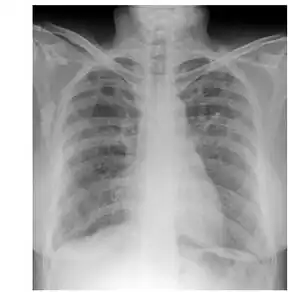

| Chest radiograph shows bilateral nodular shadows | |